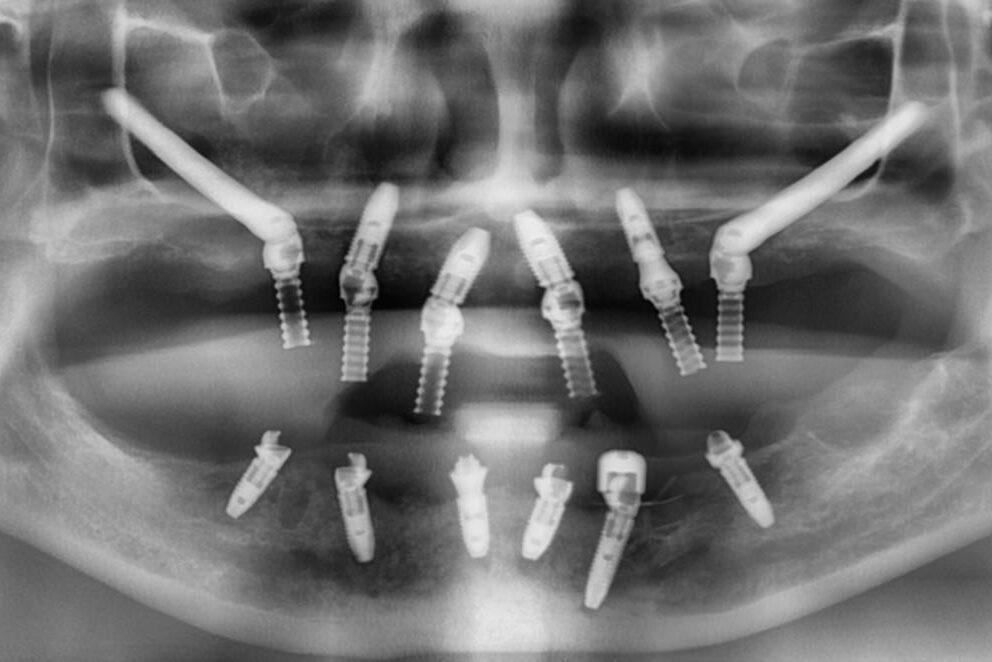

- 整個上顎骨嚴重萎縮者:可能需使用兩支或四支顴骨植體,搭配前方的普通植體,形成所謂的 Zygoma + All-on-4 混合系統(Hybrid Concept)。

📸 CBCT 斷層掃描是關鍵。需判斷:

- 上顎前方是否還有足夠骨質?

- 顴骨高度、厚度與位置是否能安裝植體?

- 是否有鼻竇纖維化、過去手術疤痕等風險?